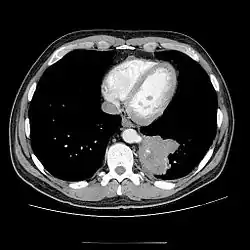

Chest CT showing pulmonary sequestration

• CT scans have 90% accuracy in the diagnosis of pulmonary sequestration.

• The most common appearance is a solid mass that may be homogeneous or heterogeneous, sometimes with cystic changes.

• Less frequent findings include a large cavitary lesion with an air-fluid level, a collection of many small cystic lesions containing air or fluid, or a well-defined cystic mass.

• Emphysematous changes at the margin of the lesion are characteristic and may not be visible on the chest radiograph.